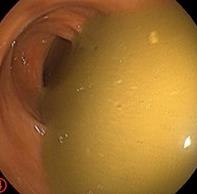

摘要:目的 探讨利那洛肽联合西甲硅油与复方聚乙二醇电解质散(PEG)对便秘患者肠道清洁效果的有效性和安全性。方法 采用前瞻性随机对照试验,通过单盲法,纳入2023年4月-2024年8月于该院消化内镜中心行结肠镜检查的便秘患者383例,随机分为常规组(128例)、实验A组(128例)和实验B组(127例)。常规组采用3 L PEG(Ⅰ)溶液,实验A组采用290 μg利那洛肽 + 2 L PEG溶液,实验B组采用290 μg利那洛肽 + 30 mL西甲硅油+2 L PEG溶液。比较3组患者的肠道准备效果[Boston肠道准备量表(BBPS)评分和去泡效果]、病变检出率、首次排便间隔时间、排便次数、盲肠插管成功率、进镜时间、退镜时间、不良反应发生率和重复检查意愿等。结果 3组患者BBPS评分比较,差异无统计学意义(P > 0.05);实验B组的去泡效果评分明显低于常规组和实验A组,差异均有统计学意义(P < 0.05);实验B组的病变总检出率和息肉检出率明显高于常规组和实验A组,差异均有统计学意义(P < 0.05);常规组的首次排便间隔时间明显长于实验A组和实验B组,差异均有统计学意义(P < 0.05);3组患者排便次数比较,差异无统计学意义(P > 0.05);3组患者盲肠插管成功率均为100.0%,进镜时间相当,差异均无统计学意义(P > 0.05);实验B组的退镜时间明显短于常规组和实验A组,差异均有统计学意义(P < 0.05);常规组腹胀腹痛发生率和不良反应总发生率明显高于实验A组和实验B组,差异均有统计学意义(P < 0.05);常规组重复检查意愿率明显低于实验A组和实验B组,差异均有统计学意义(P < 0.05)。结论 290 μg利那洛肽联合30 mL西甲硅油与2 L PEG溶液方案在便秘患者肠道准备上具有优势,较3 L PEG溶液和290 μg利那洛肽+2 L PEG溶液方案,可获得更好的肠道清洁效果,且安全性和患者重复检查意愿率高,可作为便秘患者肠道准备的推荐方案。